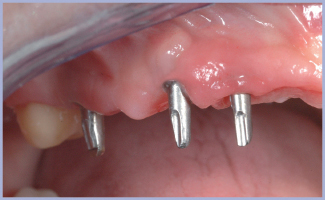

Alla riapertura (fig. 18), valutata la stabilità degli impianti e posizionati i tappi di guarigione (fig. 19), la paziente veniva controllata settimanalmente per valutare lo stato di guarigione dei tessuti e scegliere il momento opportuno per il rilevamento delle impronte; manovra eseguita con estrema velocità e con la possibilità di rilevare contestualmente anche elementi dentali rispetto alle tecniche avvitate (fig. 20).

- Fig. 18

- Fig. 19